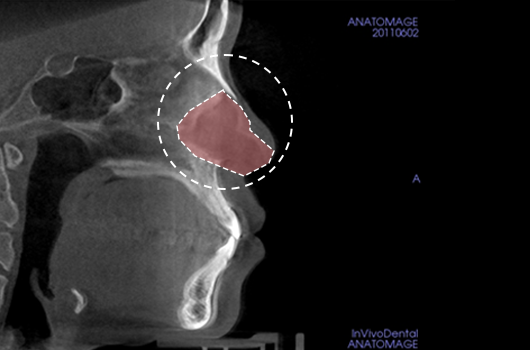

Importance of 3D-CT Scan in Rhinoplasty

During every consultation for rhinoplasty, Braun Plastic Surgery Clinic uses 3D-CT scan to analyze the following issues in three dimensions: A precise surgical plan can be established, and potential side effects reduced by thoroughly understanding the size, shape, and asymmetry of the invisible portions of the nose and the nearby anatomical structures prior to surgery.

With implants made specifically for each patient with the help of 3D-CT scan, we can reduce the probability of side effects and achieve a more natural-looking appearance.

1. Analysis of septal cartilage in various sizes and shapes

Analysis of septal cartilage in various sizes and shapes